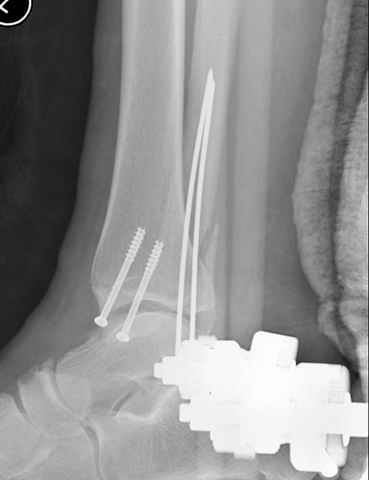

A propos fibular fixation if one is eager to stabilize it separately. In the fracture pattern a way of closed fixation by V-shaped stressed wire (advanced by colleagues from Moscow, prof. Lazarev A.F. et al.) must be excellent. We use indirect closed reduction by the external fixator. Example attached, that fibular fracture is even more suitable for plating but the wire did the job.

Второй случай сделан из одного разреза

Отправитель: Djoldas Kuldjanov, M.D. 16 Сентябрь 2004, 21:34

Pilon fracture: